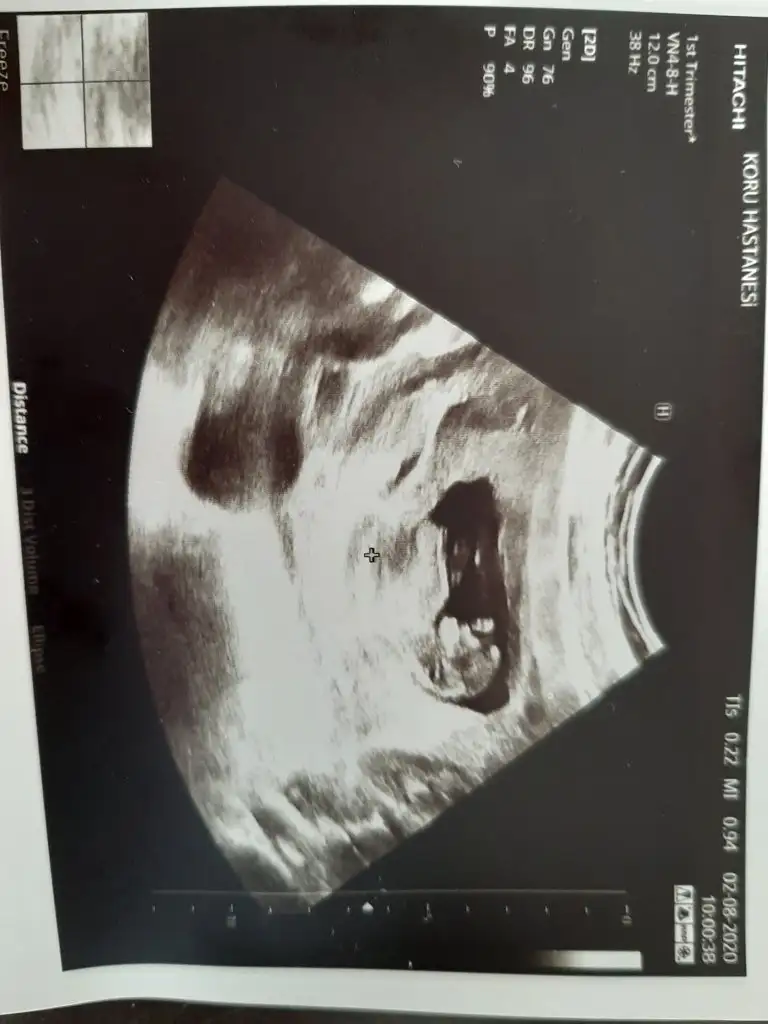

Erkeğe benzettim kafa yapısındanKızlar ilk kez bugün bebeğimi gördüm ne kadarda büyümüş çok mutlu oldumm :)

Cinsiyet tahmininden anlayan varsa tahminleri alabilirim

Bugün pazar ve bayram doktorunuz çalışıyor herhalde salı günü bizim kontrolümüzde özel devlet ultrason cihazı çok fark ediyor salı günü bende özele gideceğim Allah nasip ederseKızlar ilk kez bugün bebeğimi gördüm ne kadarda büyümüş çok mutlu oldumm :)

Bana erkek gibi geldi ama bu işi bildiğimden değil sadece öyle geldiKızlar ilk kez bugün bebeğimi gördüm ne kadarda büyümüş çok mutlu oldumm :)

Bnde erkeğe benzettimKızlar ilk kez bugün bebeğimi gördüm ne kadarda büyümüş çok mutlu oldumm :)